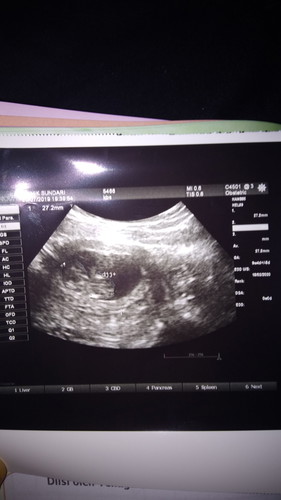

janin

Apakah 9minggu janin belom bergerak ,denyut jantung sudah keliatan,apa ngaruh sama ketuban..

9w denyut jantung malah sdh ada yg terdeteksi bun...!!!